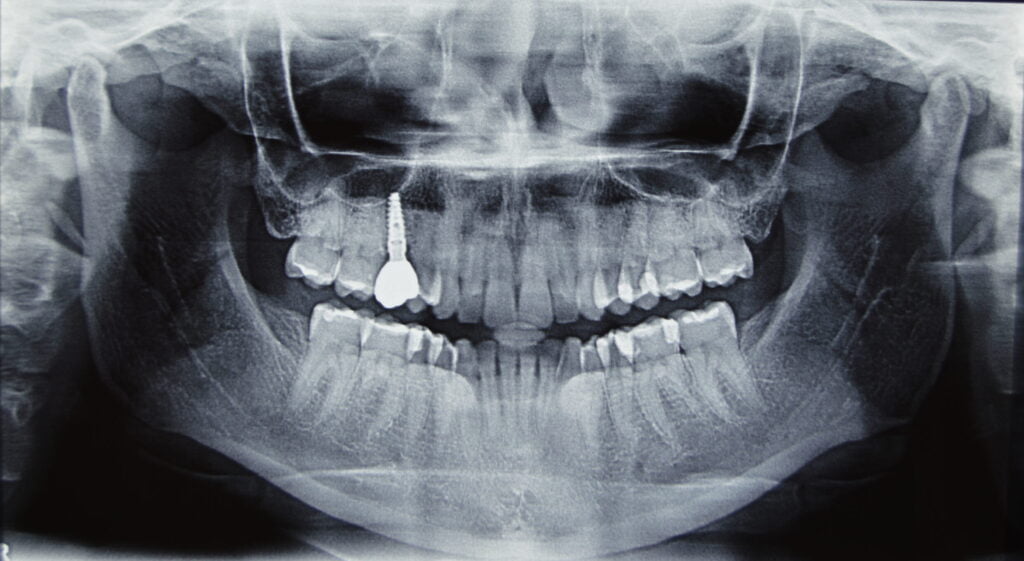

Los implantes dentales son una solución para reemplazar uno o varios dientes perdidos, consisten en un pequeño tornillo de titanio que se coloca en el hueso de la mandíbula, y luego se le une una corona dental, prótesis o un puente dental.